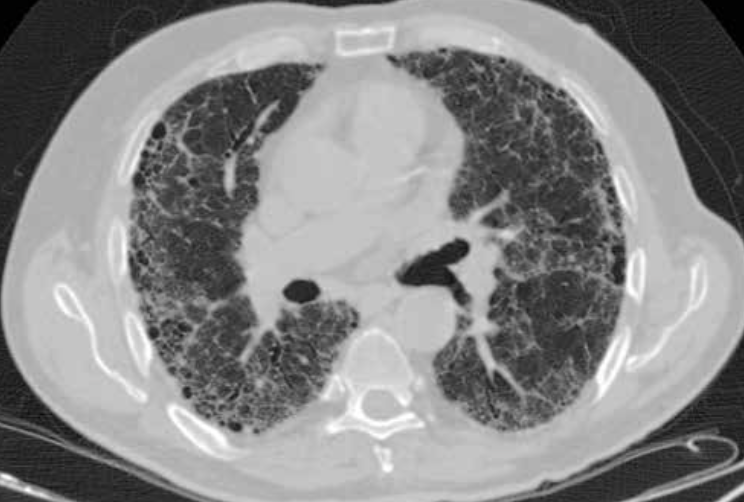

TC ventana pulmonar

Se ven mejor la vía aérea, vasos pulmonares y cisuras, pero todas las estructuras mediastínicas aparecen de un tono gris demasiado similar.